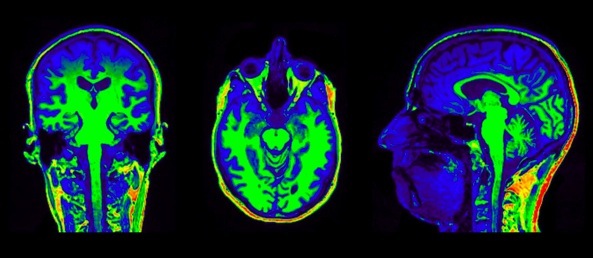

plan coronal

ou frontal

plan horizontal

plan sagittal

plan coronal

ou frontal

plan horizontal

plan sagittal